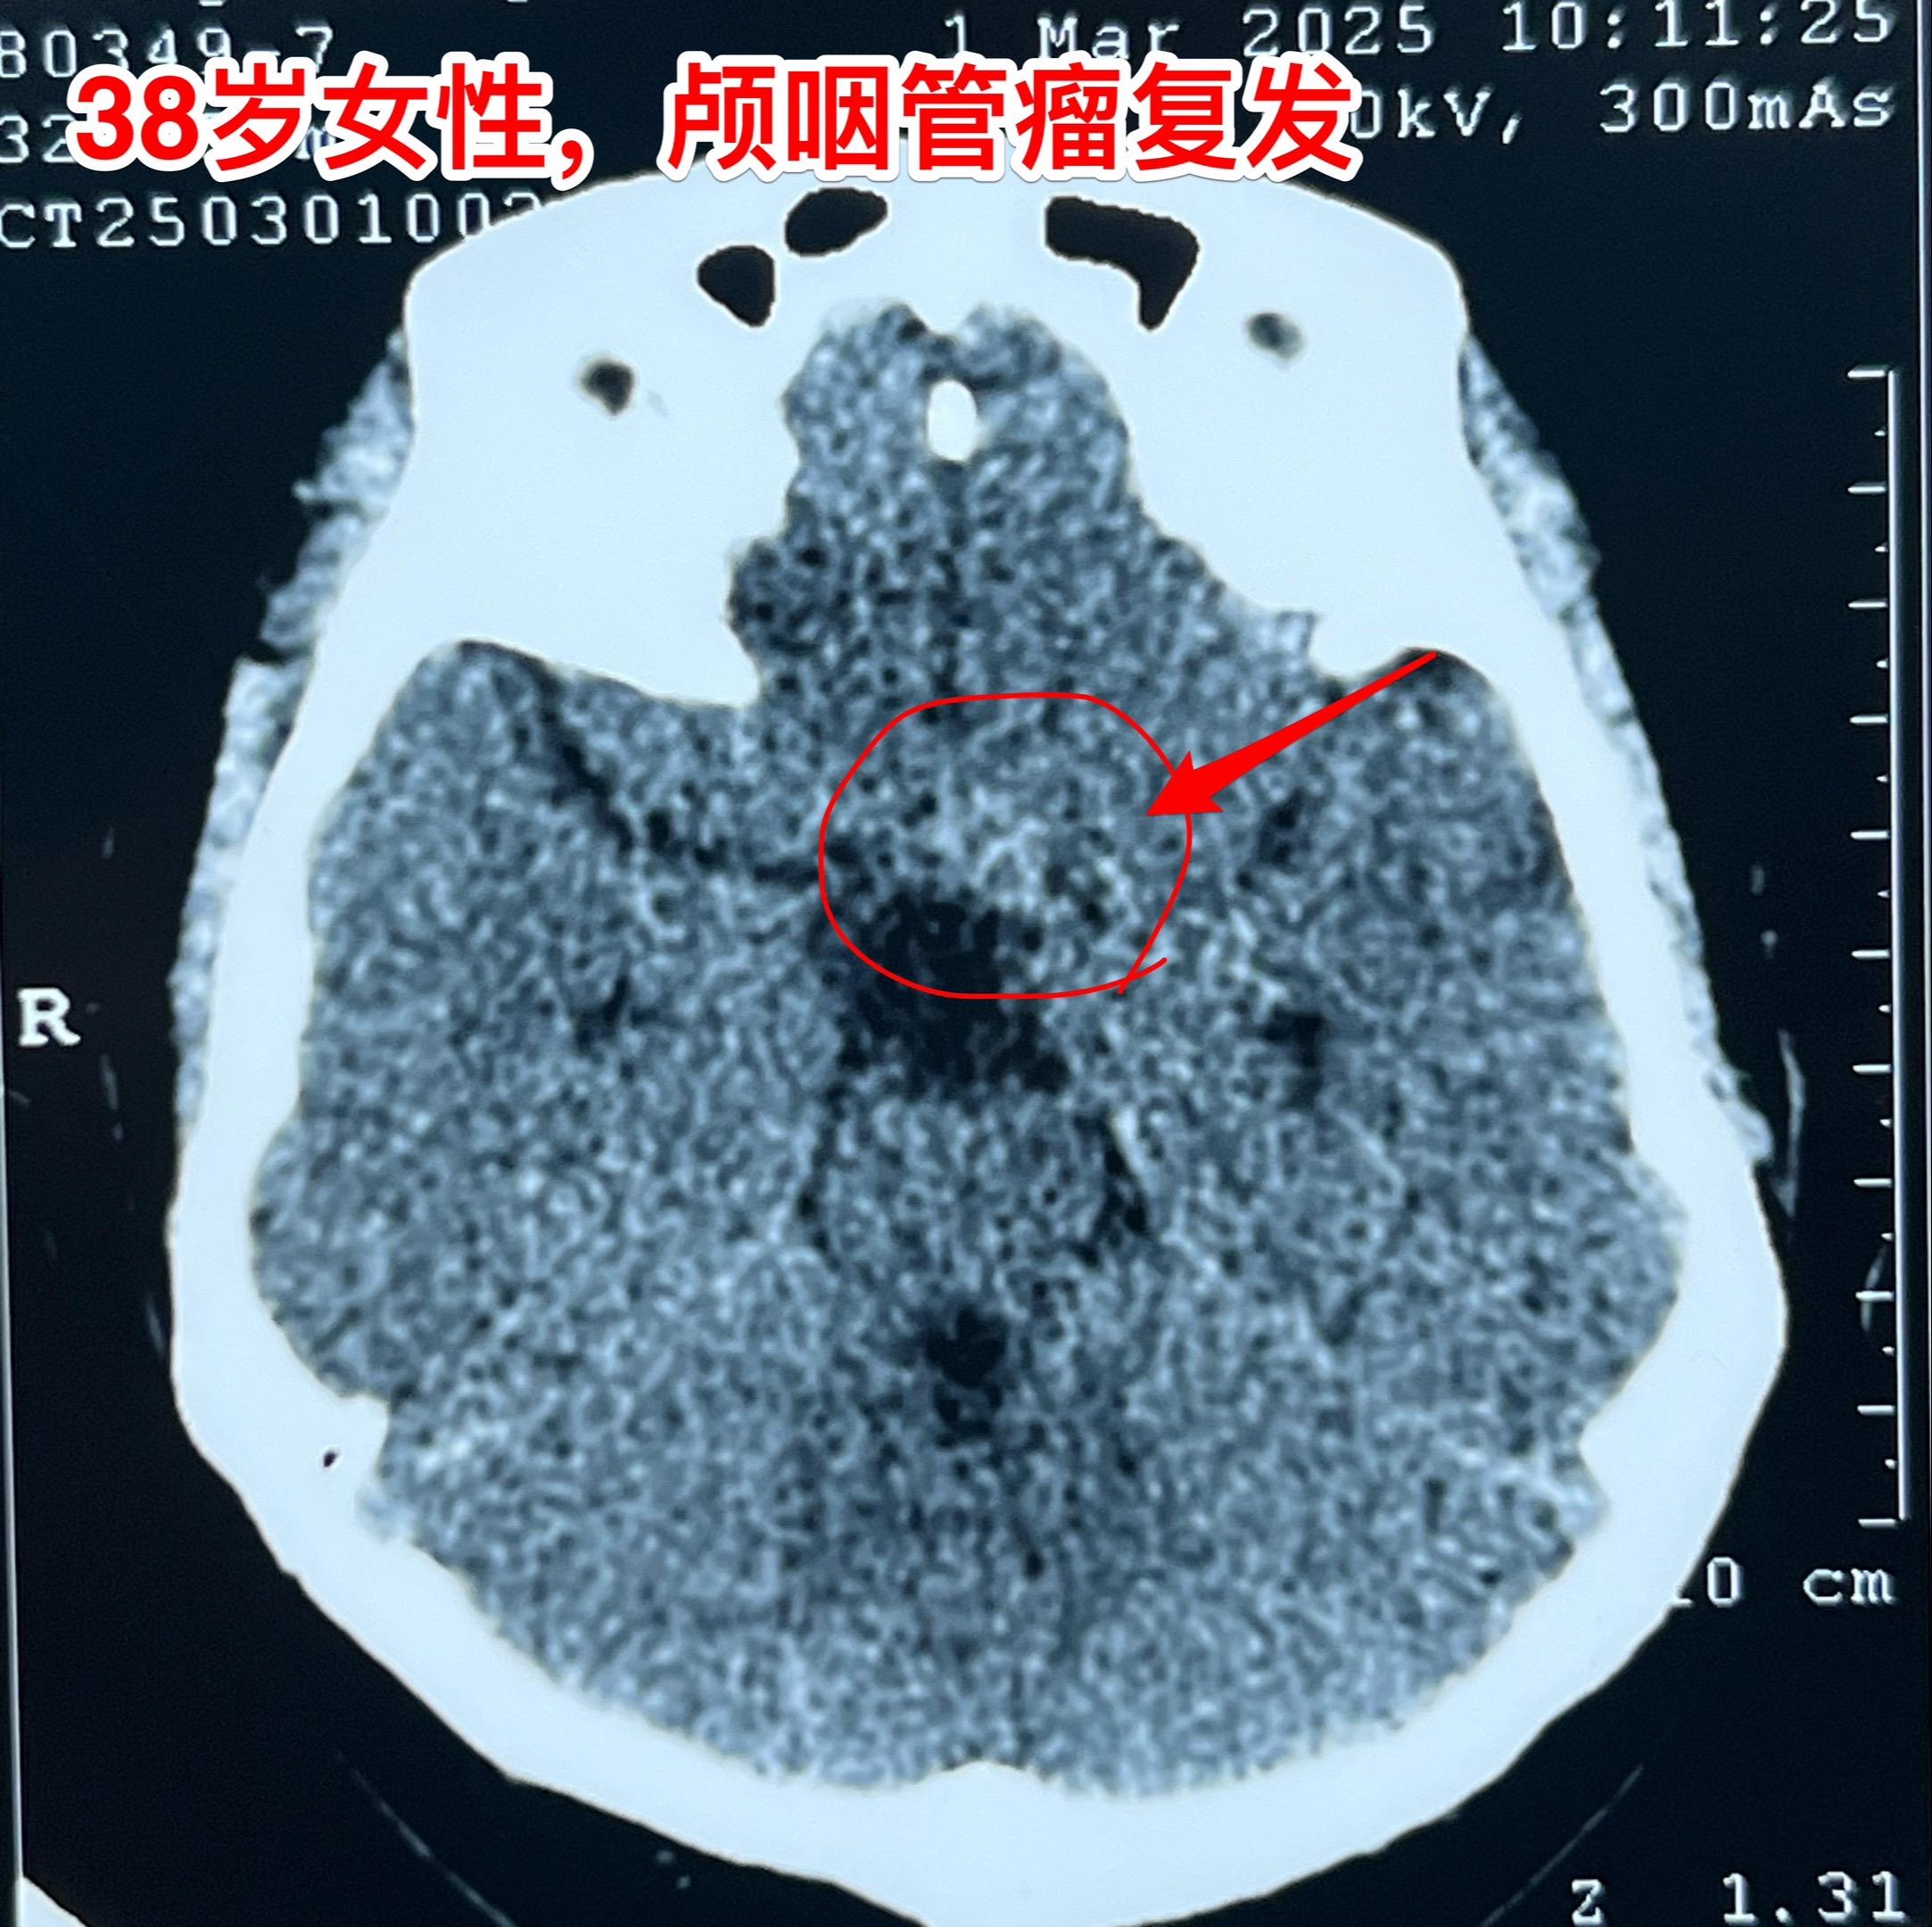

昨天的第四个手术(经鼻复发颅咽管瘤)昨日第四个完成的手术,是38岁女性,因为颅咽管瘤在北京某军医院先后作了两次经鼻内镜手术切除肿瘤。过年后发现肿瘤又复发了,见图。病人的左眼视力很差,属于无效视力。 手术结束时已是今日凌晨了!肿瘤从垂体窝向左侧生长,得到完全切除! 今日头部CT结果是满意的,病人从ICU转回了普通病房。希望肿瘤不再复发。